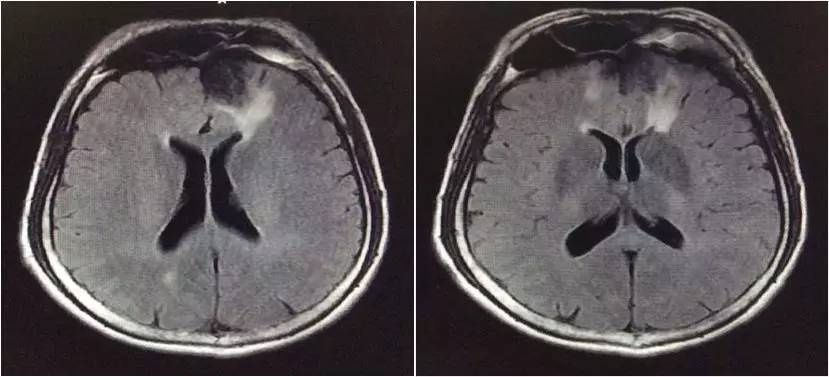

▼头颅MRI

2.脑脊液改变不除外结核感染,但头MRI改变非典型结核影像。左额叶病灶似以脑外为主,波及对侧及额窦,不排除慢性感染病灶急性破入蛛网膜下腔。左额叶病灶与脑脊液信号等信号,DWI也为低信号,说明非急性病变。

嗯,我们用的是国产的头孢曲松,没有进口的罗氏芬。DWI的高信号可以用血管炎解释吗?

血管炎都是多灶的,那个高信号太局限了,就是核心病灶周围的组织反应。不像血管炎。

真菌或结核可以引起脑底血管深穿支的炎症,有类似腔梗的影像改变。